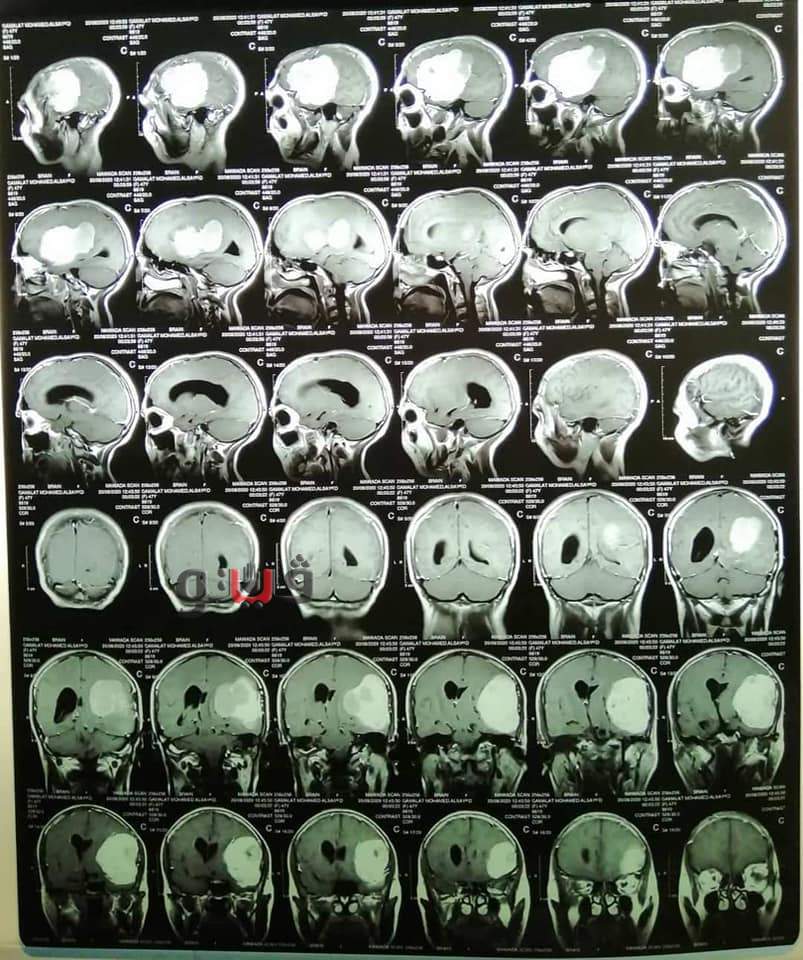

وأوضح الدكتور حسام النعمانى أستاذ ورئيس قسم جراحة المخ والأعصاب ورئيس الفريق الجراحى أن المريضة حضرت إلى عيادة جراحة المخ والأعصاب بالمستشفيات الجامعية تشكو من عدم الإتزان و بطء شديد بالكلام وصعوبة الحركة وبعد عمل الفحوصات الطبية المختلفة من رنين مغناطيسي وأشعة مقطعية وتحاليل أنسجة، تبين وجود ورم خبيث علي جدار المخ أثر على الإتزان والكلام و الحركة، على الفور تم تجهيز المريضة لإجراء الجراحة وتم إستئصال كامل للورم الخبيث بواسطة الميكروسكوب الجراحى، و المريضة حاليا بحالة جيدة بدون أى آثار جانبية، و يوجد تحسن بصورة كبيرة في الكلام والحركة.